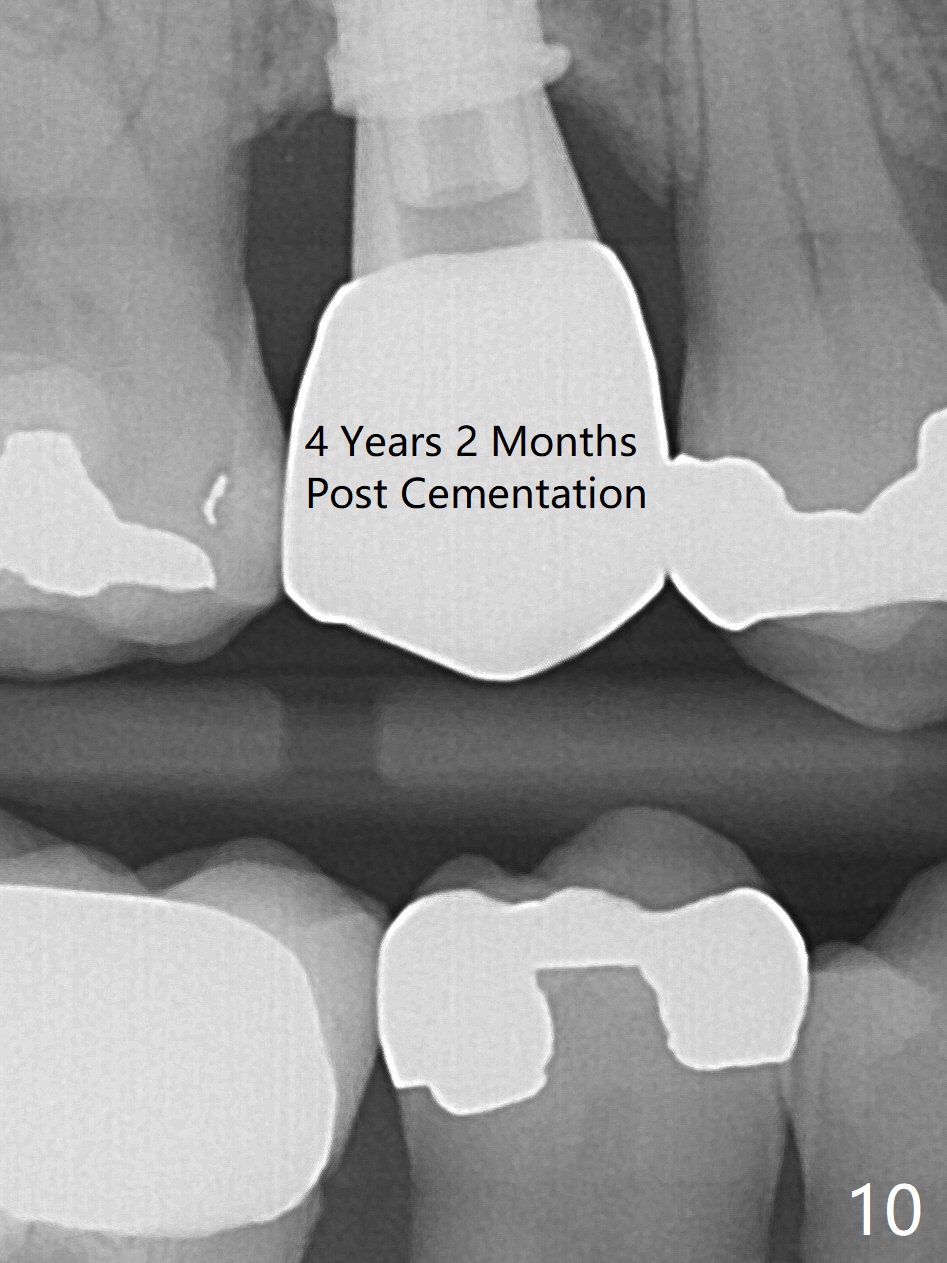

To prevent sinus lift related sinusitis, a shorter implant is going to be placed (Fig.1), approximately 2 mm beyond the apex. Following extraction, the buccal plate (Fig.3a (coronal section): B) is not only ~ 2 mm shorter than the palatal one (P), but also thinner. Since the bone density of the palatal plate is higher, without osteotomy an implant is less likely placed in the middle of the socket (S (Fig.1); Fig.3b) than buccal (Fig.3c). Therefore drills are used to form osteotomy in the apical 1/3 of the palatal slope (Fig.3d (red arrow); SM: sinus membrane). When 3.3 mm Magic Drill (MD) is in place (Fig.2), the distal surface of the sinus septum is perforated without air leakage. Demineralized allograft (.0125-.085) is placed for sinus lift (Fig.4 *) prior to placement of 4.5x11 mm implant with ~ 30 Ncm. The implant is slightly buccal to the ideal position indicated in Fig.3e (curved blue line: sinus lift). A 4.5x4(2) mm pair abutment is placed for an immediate provisional to hold mineralized allograft in the remaining socket gaps (Fig.4 arrowheads, .5-1.5 mm). A 9 mm implant may avoid sinus floor perforation on the distal slope of the 2nd premolar. The osteotomy should have been established initially as mesial as possible. In fact the patient has nasal hemorrhage while sneezing for the first 2 days postop. Although he complains of pain buccal to the implant, the gingiva appears to heal 7 days postop (Fig.5). The distobuccal papilla appears to be displaced somewhat. Raising mucoperiosteal flap is most likely associated with postop pain and esthetic compromise. The implant appears to have osteointegrated 5 months postop (Fig.6). A 4.5 mmx15° 3 mm cuff angled abutment is placed for final restoration. The distolingual portion of the implant is supported by the regenerated bone 3 years post cementation (Fig.7,8). There is no bone loss 4 years 2 months post cementation (Fig.9,10).